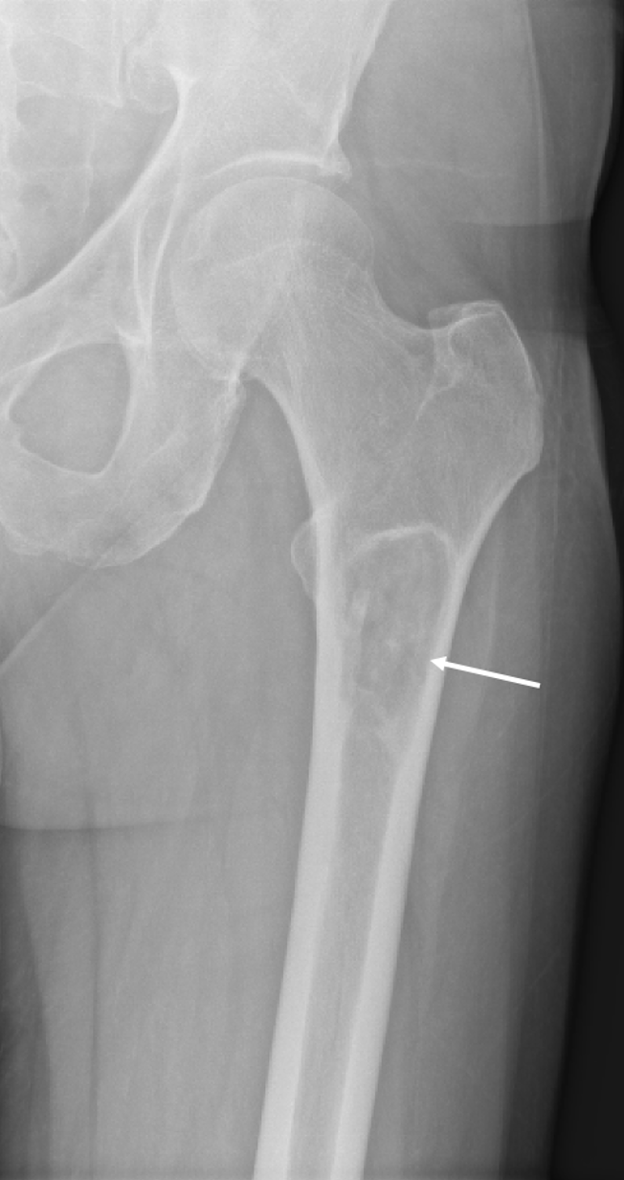

Diagnostic testing. The patient’s initial radiographs from December 2023 demonstrated a lucent lesion (Figure 1) in the proximal femur with cortical thinning, later progressing to a subtrochanteric fracture (Figure 2) and cortical destruction with expansion (Figure 3)1,2, corresponding with biopsy proven fibrous dysplasia with secondary cystic changes.

Figure 1. Initial plain radiograph of left proximal femur. Lucent lesion (white arrow) in the proximal left femur with cortical thinning.